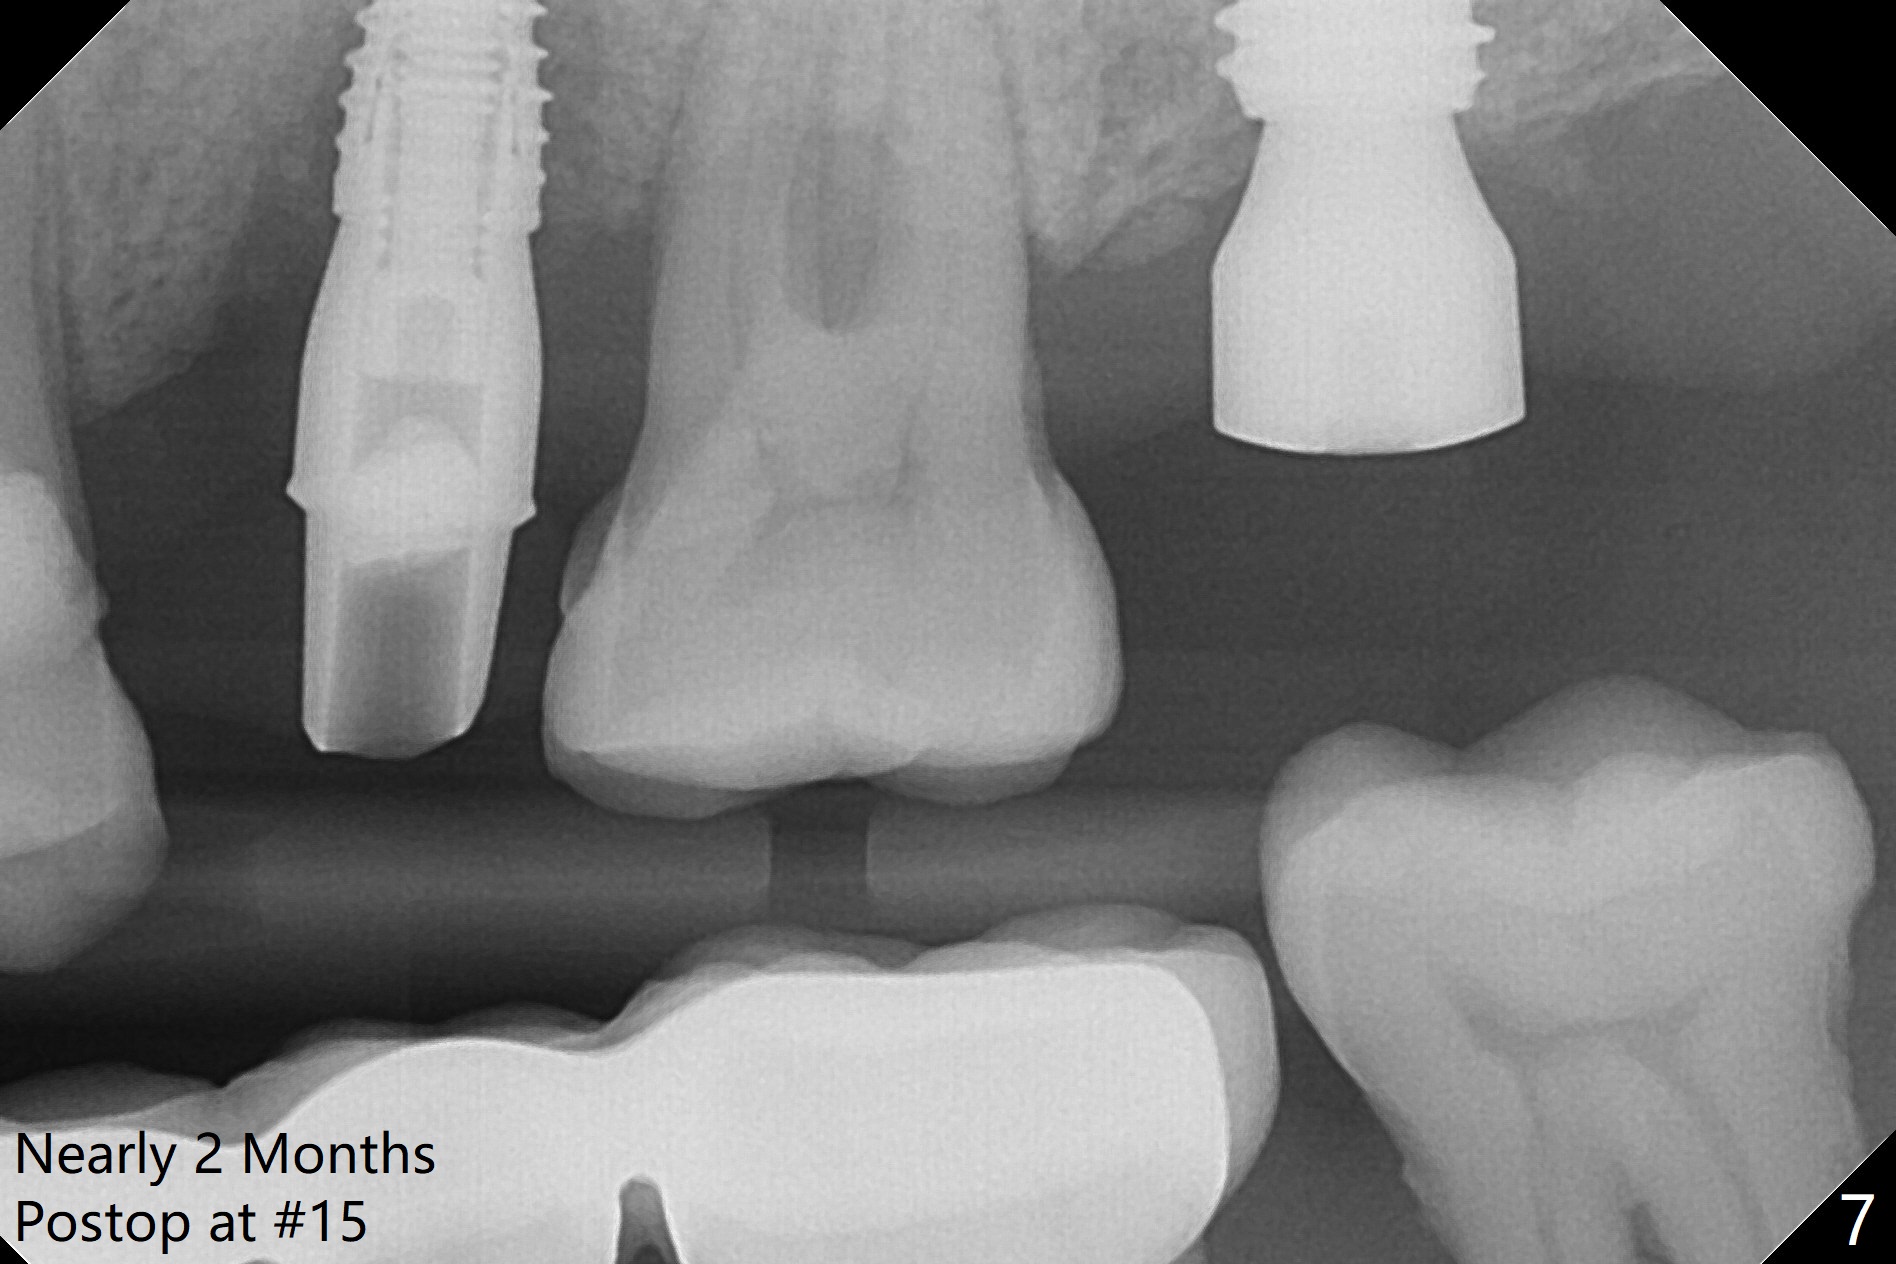

A 1.2 mm initial drill is used to start osteotomy at the site of #15 (Fig.1). After moving the osteotomy distally (with Lindamann bur), the osteotomy is enlarged by DIO Bone Expanders until 2.4/3.7 mm for 18 mm (gingival level) (Fig.2). Following the expander 3.0/4.4 mm, a 5x13 mm UF implant is placed supracrestal (Fig.3,4). After deepening the osteotomy with 3.8 mm drill for 3 mm, the implant is placed deeper by ~ 2 mm (Fig.5 arrow). Since the tooth #18 is supraerupted, a healing abutment (5.5x12(3) mm) is placed (Fig.6: H); the gingiva adapts to the abutment well. Suture is not necessary. The bone remains stable 2 and 4.5 months postop (Fig.7,8). Impression is taken. A crown is delivered nearly 6 months postop (08/07/2017). While there is minimal bone loss at #13 and 15 three years and 4 months post cementation, the tooth #14 and 18 are mobile (Fig.13,14, #13).